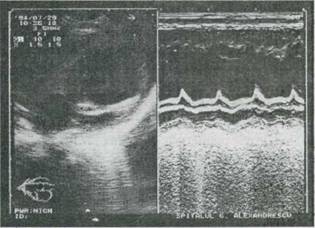

Fig. 9-21. Cardiomiopatie dilatativa la un sugar în vârsta de 4 luni. Echocardiografie 2-D (axul lung parastemal) si mod M evidentiaza: A. Dilatare importanta ventriculara stânga (57 mm la sfârsitul diastolei) cu bombarea septului ventricular spre cavitatile drepte. B. Motilitate redusa a septului ventricular si peretelui posterior; amplitudine redusa de deschidere a valvei mitrale.